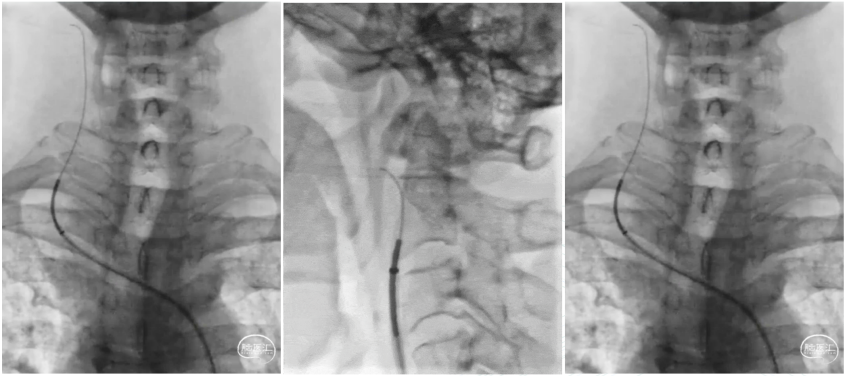

A coaxial system composed of a glidewire, a 125 cm MPA1 catheter, and a 6F 90 cm sheath was advanced into the right common carotid artery. The long sheath was positioned at the proximal bifurcation of the right CCA. The occlusion was crossed using the glidewire and MPA1 catheter, followed by advancement of the 6F 115 cm Zenith Distal Access Catheter through the occlusion.

Multiple aspiration passes were performed from the C1 to C4 segment of the right ICA using Zenith Distal Access Catheter, retrieving a large volume of dark, organized thrombus. Repeat angiography revealed severe residual stenosis (~70%) at the C1 segment with a suspected dissection and poor visualization distal to the cavernous segment.

An EDPA-060-190 embolic protection device was introduced via Zenith Distal Access Catheter and positioned in the C2 segment of the ICA. Under fluoroscopy, the filter was seen to open and appose well to the vessel wall. A 7 mm × 50 mm self-expanding stent was deployed at the site of residual stenosis with precise positioning. Post-deployment angiography demonstrated resolution of the dissection and significant improvement of C1 segment stenosis. The protection device was retrieved without visible embolic debris.